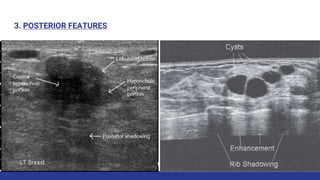

3. POSTERIOR FEATURES

• #37 enhancement, shadowing. Posterior features represent the attenuation characteristics of a mass with respect to its acoustic transmission, also of additional value. Alone it has little specificity.